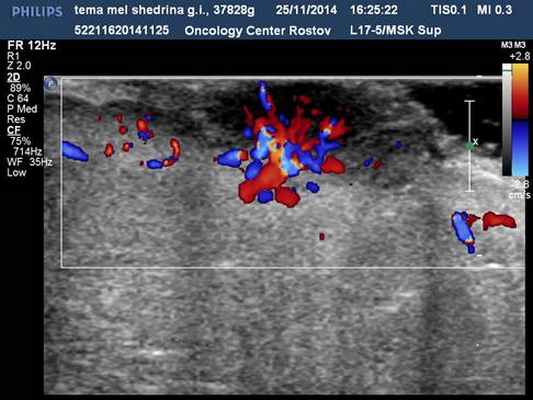

Узловые формы меланом (у 28 чел.) кожи в 100 % наблюдений характеризовались округлой формой, пониженной эхогенностью, неоднородной структурой, инвазивным ростом, наличием патологического артерио-артериального кровотока различной степени интенсивности (низкой 5 %, средней 14 %, высокой 81 %) с диапазонами максимальных артериальных скоростей (МАС) на уровне от 9,23 до 75,2 см/с, индексом периферического сосудистого сопротивления 0,2–0,6 (рис.1, 2).

Рис. 1. Узловая меланома кожи, ЦДК. Патологическая неоангиоархитектоника в образовании и в периферической зоне